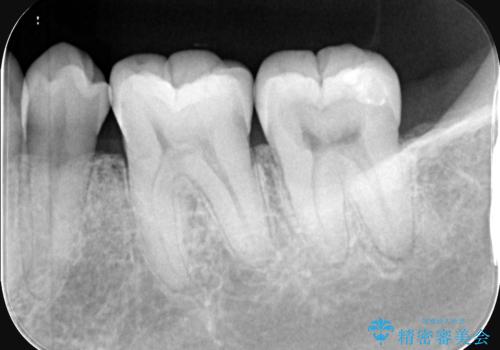

左下7番目の歯の頬側に大きな穴(う蝕によるもの)が空いており、う蝕の範囲が大きく神経を及ぼしている可能性も説明し生活歯髄療法とクラウンでの補綴治療を行うこととなりました。

治療に入る前に歯髄診断を行った結果、正常反応を示しました。

左下7頬側歯頚部に大きくできたう窩内のう蝕を除去していき、生活歯髄療法(間接覆髄法)を行いました。